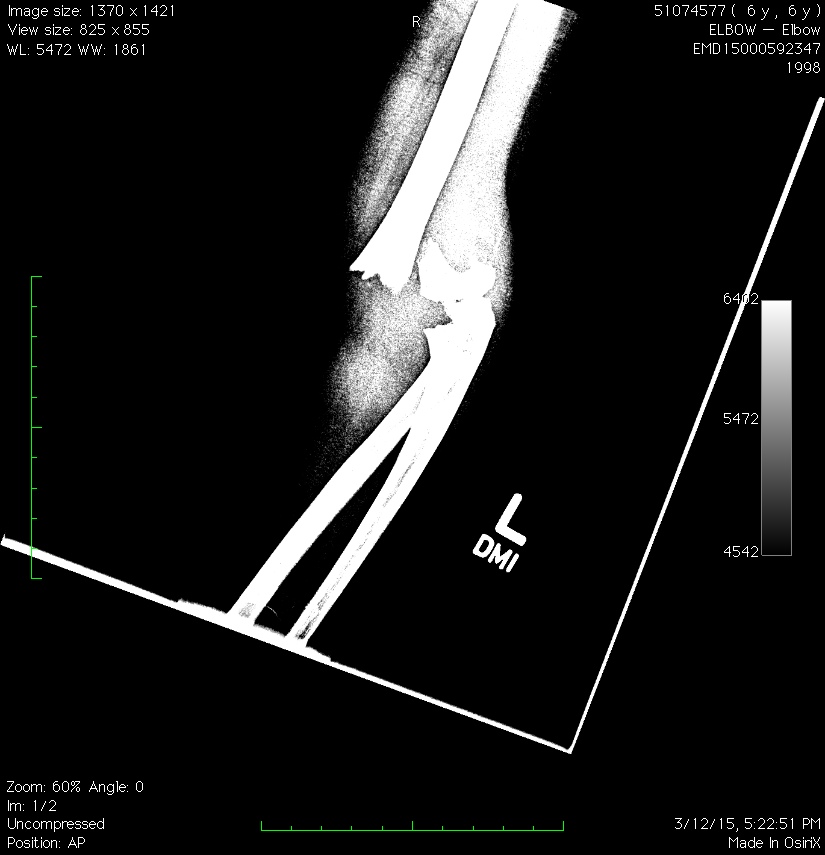

After a while, we had been at our second hospital of the night for around four hours and it was, at last, time to Maddo to go into the operating room. Her break was serious enough that the on-call orthopedic surgeon felt the need to come in to the hospital and fix things up, even as he needed to have at San Francisco Airport at 9 a.m. for a flight to India, where he was slated to teach a technique for setting a broken arm without having to perform invasive surgery…a technique he hoped to perform on Maddo.

My wife and I were pretty beat by this point. And we were regular zombies when, at about 2:15, the doctor found us in the hospital cafeteria where we were passed out in a booth like a pair of drunken hobos. The procedure went without a hitch. Best of all, the doctor was able to, in effect, jam the broken bone back in place and secure it with three pins without having to cut into the arm at all.